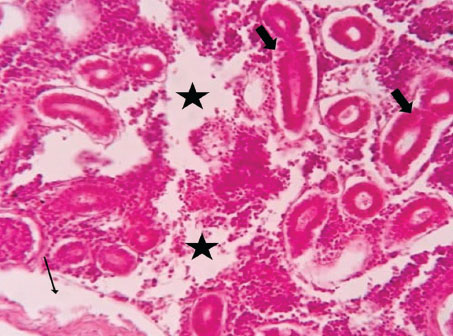

ABSTRACTBackground: The Mediterranean Sea has undergone significant ecological changes in recent decades, partly due to the introduction of non-native species. Lagocephalus sceleratus is an invasive Lessepsian species widely distributed in the Mediterranean, increasingly abundant along the Libyan coast, and potentially exposed to chronic environmental stressors. This species represents an important model for baseline pathological assessment in newly colonized marine environments. Aim: This study provides a descriptive histopathological assessment of kidney and gill tissues in adult L. sceleratus to document baseline tissue alterations without inferring direct environmental or pollution-related causation. Methods: A total of 150 adult specimens were collected from four Libyan coastal locations. Tissues were processed using standard histological techniques and evaluated semi-quantitatively (+, ++, +++) for lesion severity. Lesion severity grades were converted into ordinal numerical data and summarized using descriptive statistical approaches only. Results: Kidney tissues exhibited tubular degeneration, Bowman’s capsule dilatation, vascular congestion, extensive melanomacrophage centers (MMCs), and inflammatory lesions. Gill tissues showed disorganization of secondary lamellae, epithelial hyperplasia, edema, aneurysmal dilatations, vascular congestion, and MMC proliferation, some of which were associated with histologically observed parasitic structures. Conclusion: The observed alterations represent descriptive baseline tissue changes and should not be interpreted as direct evidence of pollution or specific environmental stressors. These findings provide reference data for future comparative pathological and ecological studies. Keywords: Lagocephalus sceleratus, Kidney, Gills, Histopathology, Melanomacrophage centers, Invasive species, Mediterranean Sea. IntroductionIn recent decades, the Mediterranean Sea has undergone profound ecological changes driven by the arrival and establishment of non-native marine species. Among these, Lagocephalus sceleratus has emerged as one of the most impactful Lessepsian migrants, due to its rapid geographic expansion, high ecological adaptability, and the presence of the potent neurotoxin tetrodotoxin in its tissues. This species has been widely documented to alter local fish communities, affect fisheries, and pose public health risks, making it an important target for biological and environmental assessment across the region (Katikou et al., 2022; Christidis et al., 2024). Fish are widely recognized as sensitive biological organisms in aquatic ecosystems, particularly in coastal habitats that are exposed to anthropogenic pressures such as industrial effluents, agricultural runoff, and untreated wastewater (Pinna et al., 2023). Among fish organs, the gills and kidneys are commonly regarded as sensitive to environmental stress, as they respond to physiological and pathological changes under environmentally suboptimal conditions. The gills, due to their large surface area and continuous exposure to surrounding water, are often the first tissues to exhibit structural alterations when fish encounter pollutants (Shahid et al., 2022). Histopathological changes in gills observed in polluted environments include epithelial lifting, lamellar fusion, hyperplasia, increased mucous cell density, and focal necrosis, which collectively reflect early physiological stress and potential compromise of respiratory function (Osman, 2010; Shahid et al., 2022). Similarly, the kidneys play crucial roles in osmoregulation, excretion of metabolic waste, and detoxification, making them highly vulnerable to chronic or systemic toxic effects (Wahidi et al., 2025). Documented renal lesions associated with chemical exposure include tubular deterioration, glomerular shrinkage, interstitial edema, and infiltration of inflammatory cells. These structural alterations often coincide with underlying biochemical disruptions, such as oxidative stress, impaired detoxification pathways, and activation of apoptotic mechanisms (Bernet et al., 1999; Authman, 2015). Despite the growing body of research on the ecological and toxicological implications of L. sceleratus, detailed histopathological assessments of this species remain scarce, especially in the southern Mediterranean basin, where environmental conditions and pollution profiles may differ from those in other regions. To date, detailed tissue-level studies of L. sceleratus from the southern Mediterranean are lacking, which limits the understanding of how this invasive species responds physiologically to local environmental stressors (Shakman et al., 2019; Ulman et al., 2021; Mohmmed et al., 2023). Accordingly, the present study aims to provide a comprehensive descriptive evaluation of histopathological changes in the kidneys and gills of L. sceleratus. The study is designed as a baseline histopathological assessment, focusing on tissue-level alterations without establishing causal links to environmental pollution or physicochemical stressors. By documenting structural aberrations and pathological features, this study contributes reference data for future monitoring and comparative studies in Mediterranean coastal ecosystems. Materials and MethodsSample designA total of 150 adult specimens of L. sceleratus, including both sexes, were collected from four Libyan coastal locations: Talamitha (n=39), Susah (n=34), Ain El-Ghazala (n=30), and Khalij Al-Bambah (n=47). Fish ranged in total length from 51 to 66 cm and in weight from 1.5 to 3.5 kg. Only apparently healthy adults were included, while juveniles were excluded to avoid age-related histopathological variation. Sampling was conducted opportunistically with assistance from local fishermen. All specimens were collected within a comparable seasonal window to minimize seasonal histopathological variability. Sex was recorded when possible; however, sex-based histopathological comparisons were not performed, as this was beyond the descriptive scope of the study. Fish were transported on ice at +4°C and examined in the Pathology Laboratory, Faculty of Veterinary Medicine, Omar Al-Mukhtar University (Mohmmed et al., 2023). Specimens were collected from a range of depths (0.5–70 m), with the majority from shallow waters (<10 m) and a subset (approximately 50 fish) from deeper locations (>30 m). Environmental physicochemical parameters such as temperature, salinity, and dissolved oxygen were not measured; therefore, no direct associations between histopathological findings and environmental variables were assessed. Tissue processing and histopathological examinationTissue specimens were fixed in 10% neutral buffered formalin for 24 hours. Following fixation, the samples were transferred to 70% ethanol for storage at room temperature. Subsequently, the tissues were processed for routine histopathological examination following standard procedures (Paul and Chanda, 2017). Paraffin embedding was performed, and 5 µm-thick sections were prepared using a microtome. Sections were stained with hematoxylin and eosin (H&E) and examined under a light microscope. Photomicrographs of representative lesions were captured using a high-resolution digital camera. Histopathological alterations were evaluated using a semi-quantitative scoring system adapted from Hose et al. (1996), Moshaie-Nezhad et al. (2021), and Alshailabi et al. (2023), where lesion severity was graded as mild (+), moderate (++), or severe (+++). Lesion severity grades (+, ++, +++) were converted into ordinal numerical values (1–3) for descriptive summarization of lesion severity. Due to the descriptive baseline nature of the study and the absence of a reference control group, inferential statistical comparisons were not emphasized or applied. Lesion severity scores were therefore summarized descriptively to avoid overinterpretation of the findings. Scoring was performed independently by two experienced observers, and representative lesions were confirmed across three sections per organ to ensure consistency. Tissues with visible parasitic structures were described separately from non-parasitized tissues to avoid conflating parasite-associated lesions with non-specific tissue alterations. The functional implications of the observed lesions were interpreted in accordance with Flores-Lopes and Thomaz (2011). Ethical approvalAll animal experiments conducted in this study were approved by the Ministry of Higher Education & Scientific Research and the Libyan National Committee for Biosafety & Bioethics, Libya. All procedures were performed in accordance with the relevant ethical guidelines, with session number 21/CH/25, dated 26/05/2021. ResultsHistopathological examination of the kidneyHistopathological examination of the kidney tissues of L. sceleratus revealed multiple alterations. Prominent melanomacrophage centers (MMCs), necrotic areas, dilatation of Bowman’s capsules, and vacuolar degeneration were observed (Fig. 1), associated with interstitial lymphohematopoietic tissue (Fig. 2). Dilated and congested blood vessels and extensive MMCs were also noted (Fig. 3). Renal degeneration surrounding lymphohematopoietic tissue, large clusters of MMCs, and thickened, congested vessel walls within fibrotic areas were evident (Fig. 4). Atrophic renal degeneration with necrotic and vacuolar changes was observed (Fig. 5). Severe inflammatory infiltration of lymphatic cells and granulomas with necrotic centers, surrounded by fibrous tissue, was detected (Figs. 6–7).

Fig. 1. Histopathology of the kidney in an adult L. sceleratus showing kidney parenchyma (stars), MMCs (head arrows), necrotic tissue (thick arrows), dilatation of Bowman’s capsule (thin arrow), and vacuolar degeneration (blue arrows). ×100 H&E.

Fig. 2. Histopathology of the kidney in an adult L. sceleratus showing renal degeneration with necrotic areas (stars), severe MMCs (head arrows), and interstitial lymphohematopoietic tissue (thick arrows). ×40 H&E.

Fig. 3. Histopathology of the kidney in an adult L. sceleratus showing dilated and congested blood vessels (star) and severe MMC proliferation (head arrows). ×40 H&E.